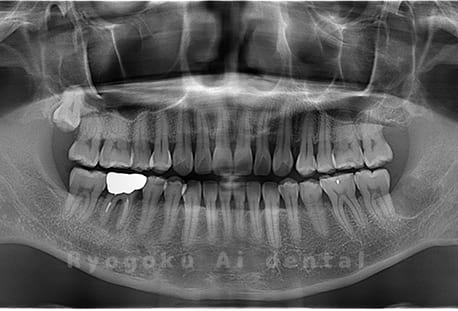

Case14

- 原因

- 重度カリエス、親知らず

- 治療内容

- 親知らずの抜歯、移植手術、マイクロエンド、ダイレクトボンディング

- 治療費用

- 220,000円

他院で親知らずと共に抜歯と診断された患者様です。親知らずの抜歯の必要性と左下奥歯の保存を試みた場合、歯の状態から根管治療、歯周外科、補綴の必要性から、移植治療を選択されました。大きな問題もなく、治療後も経過良好です。

<リスク・副作用>

治療後、痛みや違和感、出血、腫れなどが出る事があります。喫煙者、糖尿病などの方の場合、歯が生着しない場合があります。